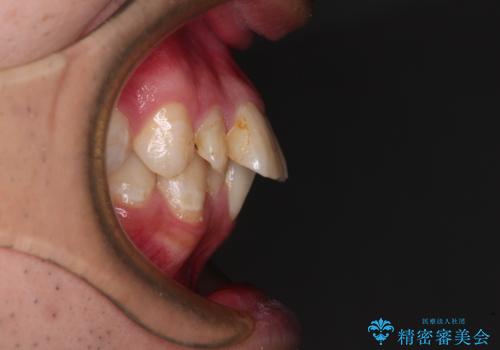

- 口元の突出感と奥歯の咬み合わせの悪さを気にして来院された患者様です。

口元はやや突出感があったため、上下左右の第一小臼歯4本を抜歯してワイヤー矯正にて抜歯矯正を行うこととしました。

また、左右ともに最後臼歯が交叉咬合になっており、外側に飛び出している上顎の最後臼歯を補助装置を利用して、積極的に内側に引き込むようにしました。